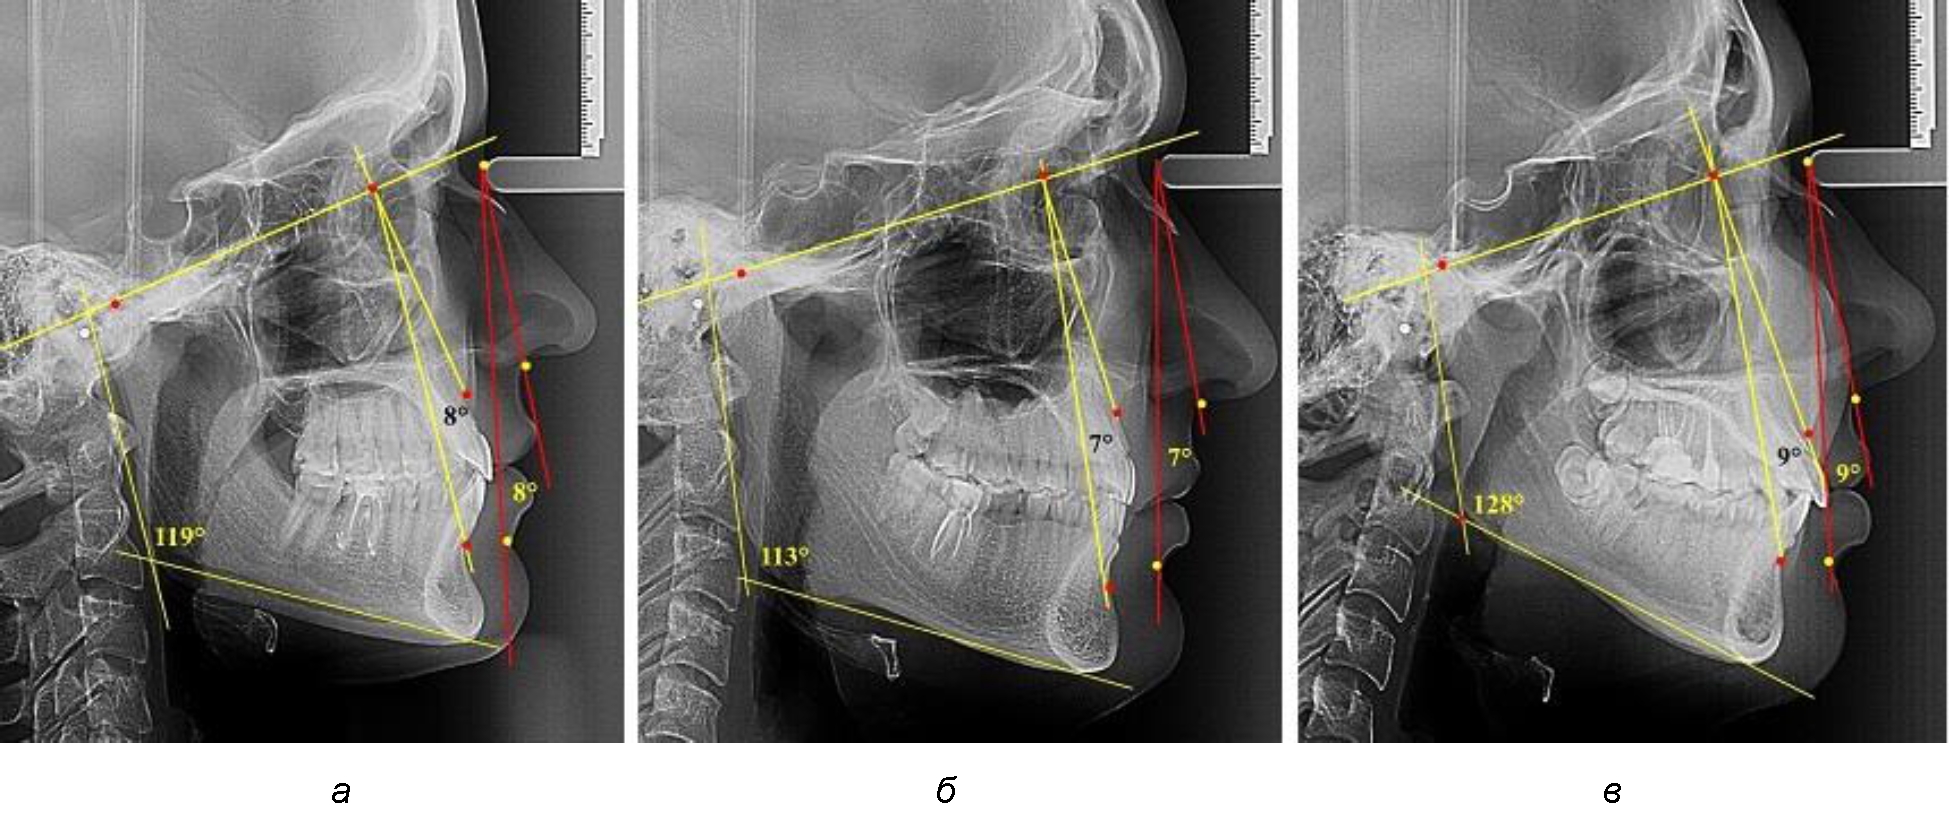

В группе людей с нейтральным типом нижнечелюстного угла величина лицевого межгнатического угла составляла (7,98 ± 0,49)° при использовании как кожных, так и костных ориентиров (рис. 3).

Рис. 3. Параметры кожного и костного лицевого межгнатического угла при нейтральном (а), горизонтальном (б) и вертикальном в типах угла нижней челюсти

В группе людей с горизонтальным типом нижнечелюстного угла величина лицевого межгнатического угла была несколько меньше и составляла (7,05 ± 0,37)° при использовании как кожных, так и костных ориентиров.

В группе людей с вертикальным типом нижнечелюстного угла величина лицевого межгнатического угла была больше, чем при других типах и составляла (9,23 ± 0,45)° при использовании как кожных, так и костных ориентиров. Таким образом, при всех типах нижнечелюстного угла отмечалось равенство параметров лицевого межгнатического угла как по кожным, так и по костным ориентирам. Полученные сведения легли в основу определения лицевого межгнатического угла на фотографиях в профиль при различных позиционных типах лица.